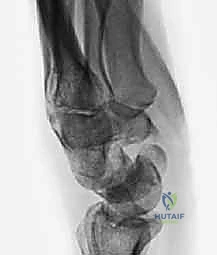

Here, we observe a classic presentation of a failed open reduction and internal fixation (ORIF) of a scaphoid nonunion. Despite surgical intervention, the biological and mechanical environment was insufficient to achieve osteosynthesis, leading to hardware failure and persistent nonunion.

Figure 1A: Failed ORIF of a scaphoid nonunion (PA view) demonstrating hardware loosening and persistent radiolucency at the fracture site.

Figure 1B: Failed ORIF of a scaphoid nonunion (Lateral view) illustrating the early signs of carpal collapse and dorsal intercalated segment instability (DISI).

Thorough preoperative planning relies heavily on high-quality orthogonal imaging. Standard posteroanterior (PA), true lateral, and scaphoid-specific views (PA with ulnar deviation and slight extension) are mandatory. These plain radiographs are assessed for the presence and location of the nonunion, the degree of cystic resorption, and the specific location of osteophyte formation and joint space narrowing.

The true lateral radiograph is critical for assessing carpal alignment and measuring the degree of Dorsal Intercalated Segment Instability (DISI). The scapholunate angle is calculated by drawing a line down the longitudinal axis of the scaphoid and intersecting it with a line perpendicular to the distal articular surface of the lunate. A normal scapholunate angle ranges from 30 to 60 degrees. An angle exceeding 60 degrees, coupled with a radiolunate angle greater than 15 degrees of extension, confirms a significant DISI deformity.

Figure 5A: Lateral plain radiograph displaying a severe DISI deformity, characterized by an extended lunate and a flexed distal scaphoid fragment.